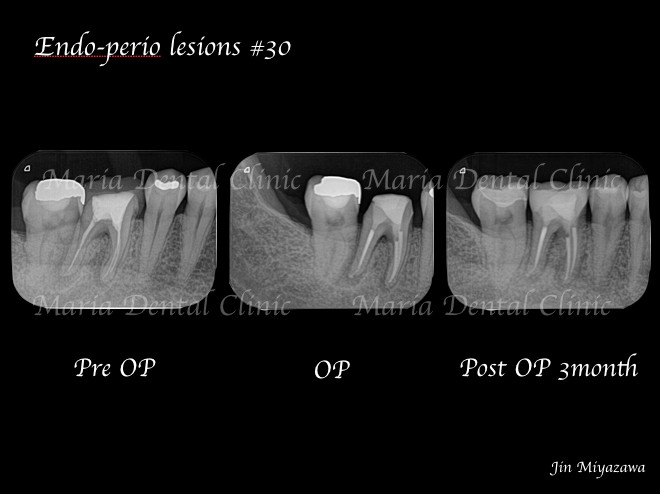

3ヶ月後のレントゲン撮影にて根尖病変の縮小、ならび違和感の消失を確認。今後最低2年間の経過観察(1年に1回)を行い、根尖周囲組織の治癒を確認していく。

歯内歯周病変とは、歯の内側(根管内)のトラブルと歯の周囲組織のトラブルが併発することを言います。この場合、歯内療法と歯周病治療、両方からのアプローチを必要とする為、確実な診査、診断、そして治療が予後を左右します。

歯内歯周病変は限局的な歯周ポケットを併発するため、歯根破折と誤診されやすい病気です。当院の精密根管治療を希望し来院される多くの患者様が、他院にて「歯根破折」と診断されたが抜歯せず歯を残したいと望まれており、実際に精密根管治療を施すことで多くの歯が残せているのも事実です。